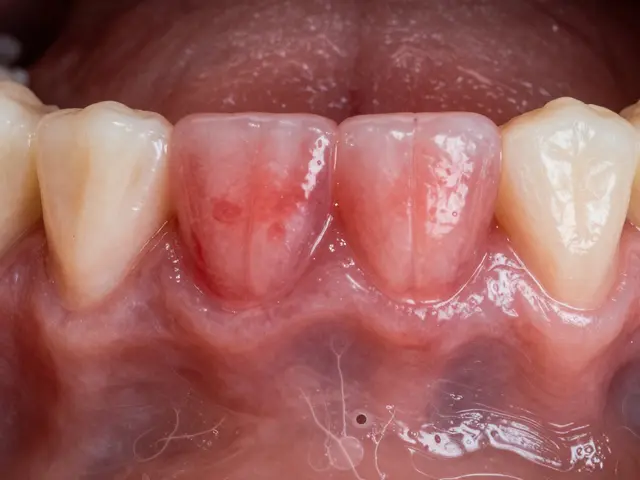

Na povrchu skloviny se děje mnohem víc, než bychom si mohli myslet. Mimo viditelných zbytků jídla a skvrn je sklovina domovem mikroflóry, tedy drobných organismů, které zde žijí v delikátní rovnováze. Nejznámějšími obyvateli jsou bakterie, které jsou součástí zubního plaku. Pokud není plak pravidelně odstraňován, může dojít k jeho mineralizaci a vzniku zubního kamene, který je pak mnohem obtížnější odstranit.

Zubní plak a jeho důsledky

Zubní plak je lepkavá, bezbarvá vrstva, která se neustále tvoří na povrchu zubů. Je složená převážně z bakterií, které se živí cukry z naší stravy a vytvářejí kyseliny jako odpadní produkty. Tyto kyseliny mohou attakovat sklovinu, což vede k demineralizaci a následně k tvorbě zubního kazu. Pravidelné a správné čištění zubů kartáčkem a zubní nití je klíčové pro odstranění plaku a zachování zdraví skloviny.